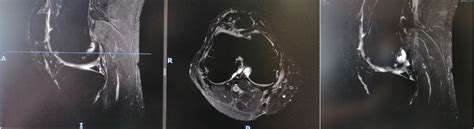

Alright, let’s kick things off by really understanding what an osteochondral injury is at its core. Picture your joint – whether it’s your knee, ankle, elbow, or even your shoulder – it’s covered in a smooth, slippery tissue called articular cartilage . This cartilage, guys, is absolutely vital; it acts like a natural cushion and lubricant, allowing your bones to glide over each other without friction, absorbing shock from daily activities and keeping everything moving smoothly. Right underneath that cartilage is a layer of bone, known as the subchondral bone . Together, this dynamic duo – the cartilage and the subchondral bone – form what we call the osteochondral unit . Now, an osteochondral injury occurs when there’s damage to both this articular cartilage and the underlying subchondral bone. It’s not just a tear in the cartilage or a bone bruise; it’s a combined injury that can range from a tiny crack or a small divot to a full-blown chunk of cartilage and bone breaking loose. This can create a defect or a lesion on the joint surface, disrupting that smooth, pain-free movement you’re used to. Think of it like a pothole forming on a perfectly smooth road – suddenly, the ride gets bumpy, and the integrity of the surface is compromised. These injuries can vary significantly in their severity, from superficial scrapes to deep, full-thickness defects that expose the underlying bone, making them quite complex to manage. The challenge with cartilage is that, unlike bone, it has a very limited blood supply, which means it doesn’t heal easily on its own. This makes osteochondral injuries particularly problematic and often requires more significant intervention than other types of musculoskeletal damage. The prevalence of these injuries is quite high, especially in active individuals and athletes, given the high impact and rotational forces joints are often subjected to. Understanding this fundamental concept is the first crucial step in grasping why proper diagnosis and treatment are so critical for long-term joint health and function. It’s about protecting those precious joint surfaces so you can keep moving freely and without pain, living your best life every single day. We’ll dive into the specifics of how these injuries happen next, so you can better identify potential risks and take preventive measures.

So, now that we know what an osteochondral injury is , let’s chat about how and why these tricky injuries happen . Knowing the causes and risk factors is super important because, for some of them, we might actually be able to take steps to prevent them or at least be more aware of the signs. Generally speaking, osteochondral injuries often stem from two main culprits: trauma or repetitive stress. Think of trauma as a sudden, acute event – like a sports injury where you twist your knee awkwardly, or a direct impact from a fall. For example, a sharp blow to the knee, a severe sprain where the bones grind together, or a dislocation of a joint can all lead to an immediate defect in that delicate osteochondral unit. In sports, especially high-impact activities like football, basketball, or skiing, these traumatic events are unfortunately quite common. The forces involved can be so intense that they literally shear off a piece of cartilage and bone, or cause a deep bruise that damages both layers simultaneously. The tricky part is, sometimes the initial trauma might not seem that severe, but the underlying damage is still there, slowly causing issues. Beyond acute trauma, repetitive stress is another major player, often leading to a condition called osteochondritis dissecans (OCD) , which is a specific type of osteochondral injury. This happens when repeated microtrauma – small, ongoing stresses to the joint – compromise the blood supply to a small area of bone, causing it to soften and eventually separate from the surrounding healthy bone, taking the overlying cartilage with it. This is more common in adolescents and young adults who are very active, as their growing bones might be more susceptible to these cumulative stresses. Factors that can increase your risk, whether from trauma or repetitive stress, include participation in high-impact sports, rapid growth spurts in adolescents, poor biomechanics or muscle imbalances that put undue stress on certain joints, and even certain genetic predispositions to weaker cartilage. Previous joint injuries, even minor ones, can also make a joint more vulnerable to future osteochondral damage. Guys, it’s not always about a single catastrophic event; sometimes it’s the little things, the repeated stresses over time, that quietly chip away at your joint health until a significant problem arises. Understanding these mechanisms helps us appreciate the importance of proper training, protective gear, and listening to our bodies when something doesn’t feel quite right. If you’re involved in activities that put your joints at risk, being proactive about injury prevention and seeking early assessment for persistent pain can make a huge difference in avoiding or mitigating the severity of these challenging injuries. It’s all about being smart and giving your joints the respect they deserve to keep you moving well into the future.